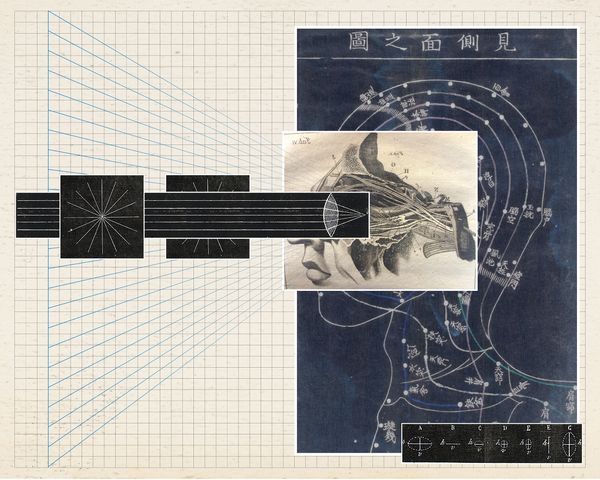

By comparing Eastern and Western myopia prevention, the project reveals how both transform health practices into systems of discipline, showing that “tradition” and “science” alike serve as tools of social and medical control.

Myopia was once racialized as an "Oriental disease".

China's standardized eye exercises combine traditional massage with mechanized discipline norms. As a state-mandated body ritual, it shapes explicit disciplinary instructions through unified acupoint stimulation and rhythmic music. This practice not only inherits the theory of traditional Chinese medicine, but also implies the contradiction of efficiency management in the industrial era. In contrast, the West uses technical means such as orthokeratology lenses and visual training to conduct individualized interventions, enforce self-monitoring through precise procedural norms, and embed invisible discipline into medicalized self-care.

Despite cultural differences, both systems enforce standardized body behaviors through unique but overlapping disciplinary logics, making them no longer just neutral health practices, but invisible mechanisms of social control. By juxtaposing these models, I reveal the commonalities between "tradition" and "science" as medical governance tools, question the right to define and interpret health behaviors, and re-evaluate how power operates in personal health management through seemingly benign preventive practices.